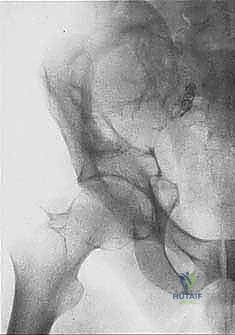

- Plain Radiography (FIG 2): While of limited value for early lesions, it provides an initial overview. As you can see in Figure 2A, we have a large lytic lesion of the right periacetabular region. Figure 2C shows a cartilage-forming lesion in the left ilium. However, plain films often underestimate the true extent of these tumors.

* CT with Intravenous Contrast and 3D Reconstruction (FIG 3): This is our workhorse for assessing bone involvement, destruction, and the critical relationship between the tumor and major pelvic blood vessels. It reveals any distortion of the pelvic anatomy and guides resectability. Figure 3A clearly shows extensive bone destruction and tumor extension into the pelvis and gluteal region. Figure 3C highlights an extensive tumor on the medial aspect of the ilium with destruction of the inner table.